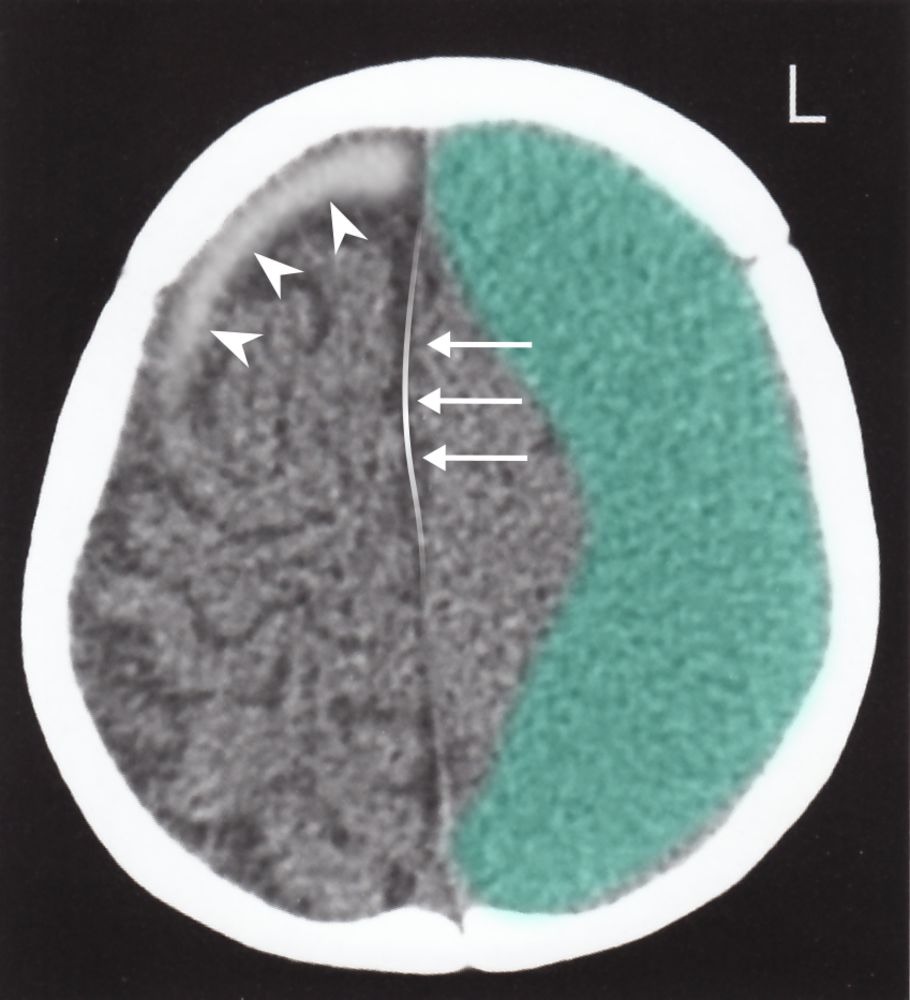

- Acute SDH is hyperdense (white)